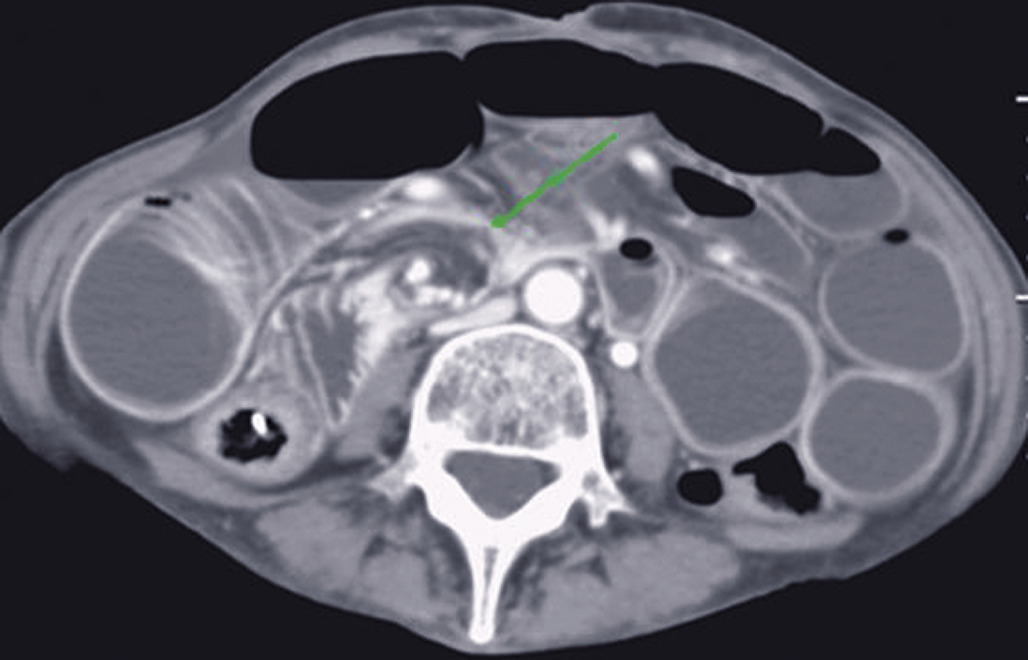

Les signes tomodensitométriques décelés sur le site de torsion sont classiquement (fig. 1 et 2) :

• anses dilatées, en forme de « U » ou de « C », à distribution radiaire ;

• présence de deux anses adjacentes collabées de forme ronde, ovale, triangulaire au niveau du site d’obstruction ;

• whirl sign, ou signe du tourbillon, qui correspond à l'enroulement des vaisseaux mésentériques et des mésos qui convergent vers le point de torsion mésentérique (fig. 1) ;

• le signe du bec, qui correspond à la visualisation, en coupe longitudinale, d’un aspect en pointe effilée reflétant à la diminution progressive du calibre intestinal jusqu'au niveau de l’obstruction (fig. 2).